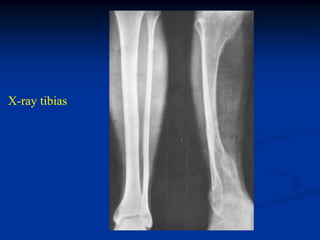

Case #584

33 year male

Maffucci’s disease

X-ray tibias

phleboliths